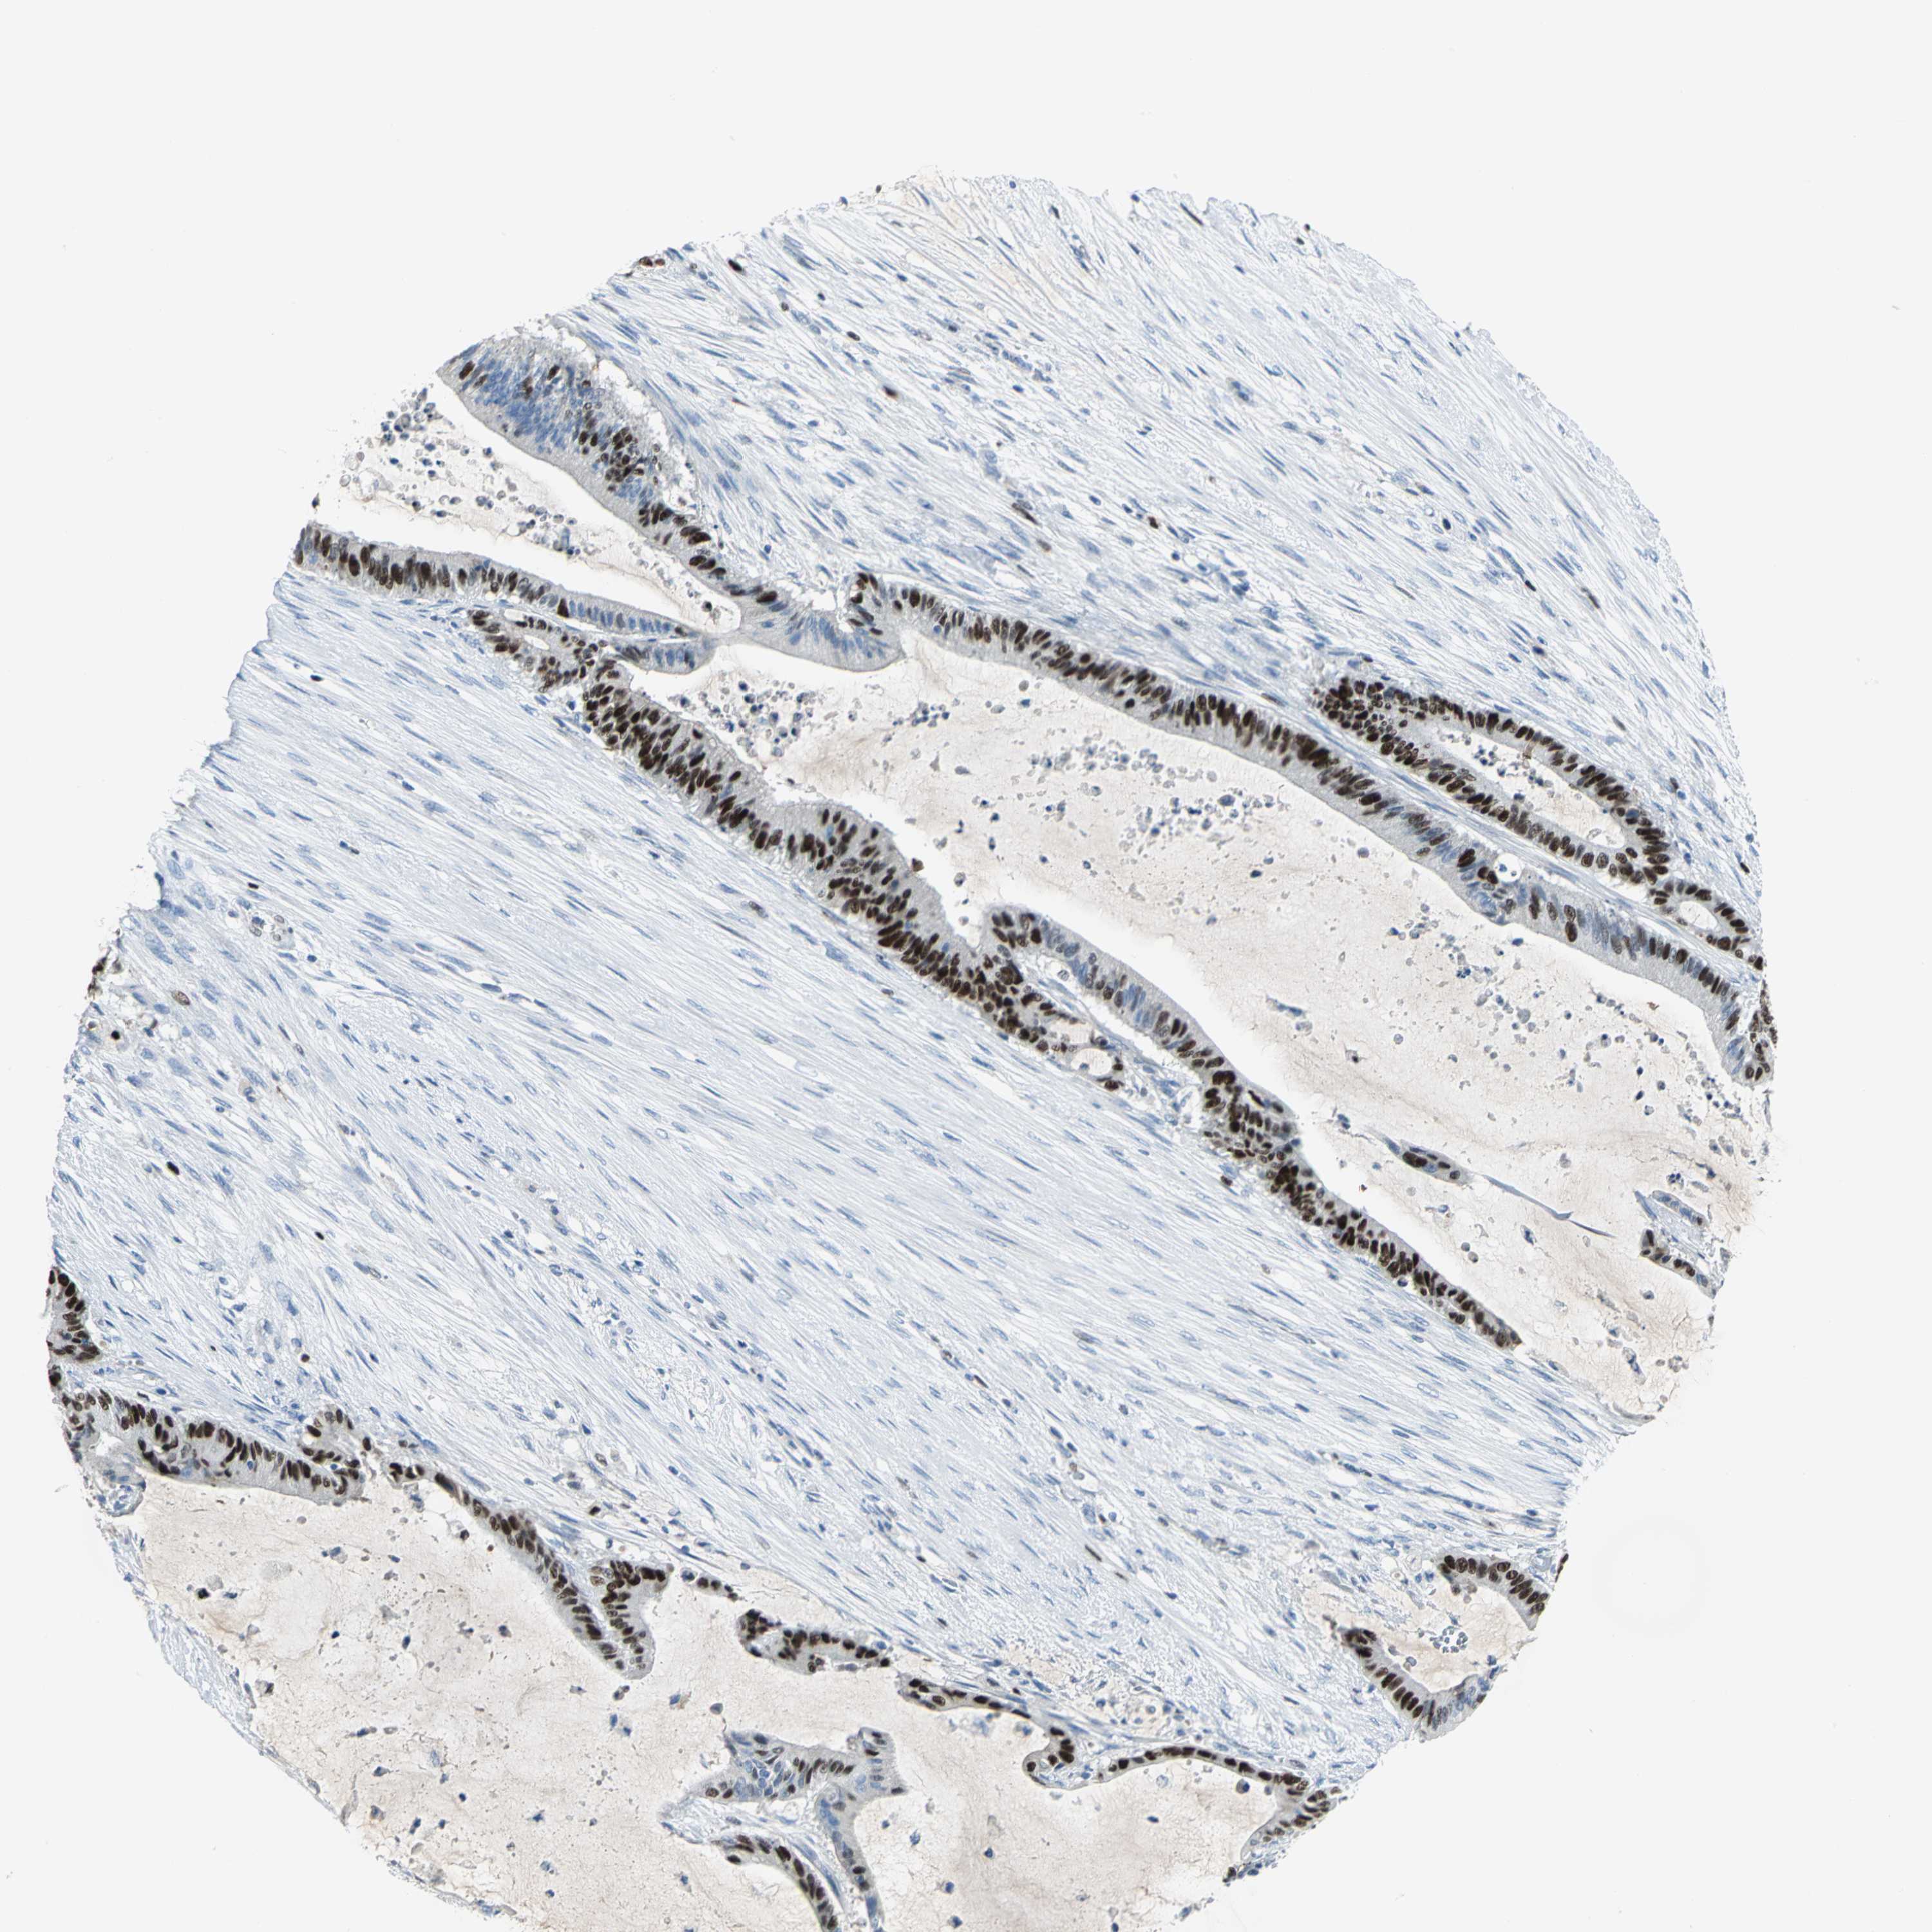

LIVER CANCER - Protein expressioni

A mouse-over function shows sample information and annotation data. Click on an image to view it in a full screen mode. Samples can be filtered based on level of antibody staining by selecting one or several of the following categories: high, medium, low and not detected. The assay and annotation is described here.

Note that samples used for immunohistochemistry by the Human Protein Atlas do not correspond to samples in the TCGA dataset.

Antibody stainingi

Antibody staining in the annotated cell types in the current human tissue is reported as not detected, low, medium, or high, based on conventional immunohistochemistry profiling in selected tissues. This score is based on the combination of the staining intensity and fraction of stained cells.

Each image is clickable and will lead to virtual microscopy that enables deeper exploration of all samples and also displays staining intensity scores, fraction scores and subcellular localization as well as patient and tissue information for each sample.

Antibody HPA004873

Antibody CAB004497

Staining

High

Medium

Low

Not detected

Intensity

Strong

Moderate

Weak

Negative

Quantity

>75%

75%-25%

<25%

None

Location

Nuclear

Cytoplasmic/membranous

Cytoplasmic/membranous,nuclear

Cholangiocarcinoma

Carcinoma, Hepatocellular, NOS